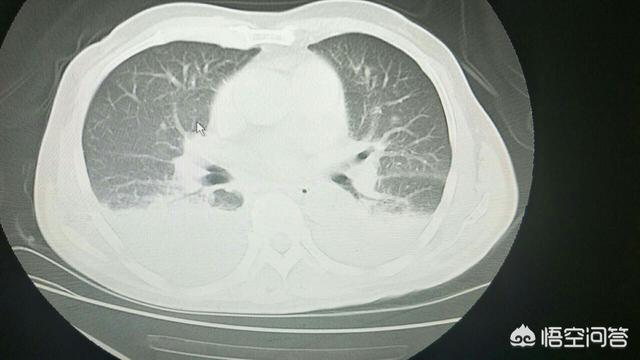

5.呼吸器系 慢性肺炎が多い。

しかし、長期的な飲酒の状況はまた、自分の体に一連の損傷をもたらすでしょう、一部の男性は、これらの傷害について知らないし、彼らは毎日少し飲むが、体に大きな損傷を与えていないとは思わないが、実際にはそうではありません、身体への長期的な飲酒の損傷が徐々に蓄積されている。